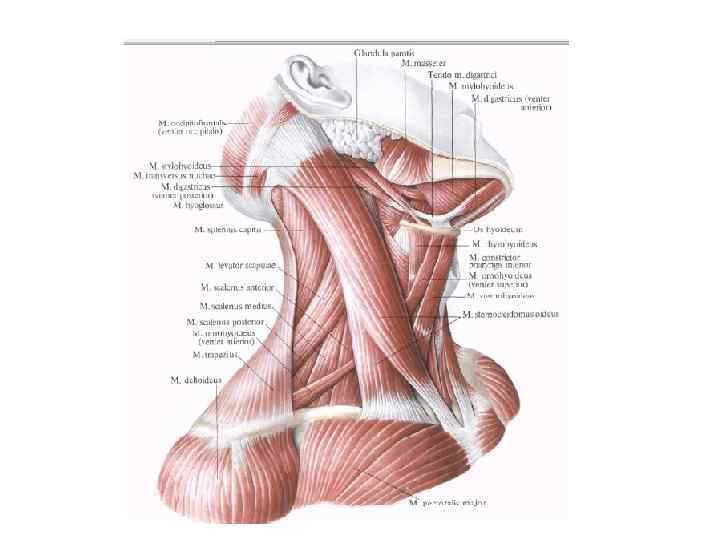

• Техника. Больного укладывают на спину с подложенным под плечи валиком, голову запрокидывают и поворачивают вправо. Разрез кожи по переднему краю грудино-ключичнососцевидной мышцы от вырезки грудины до уровня верхнего края щитовидного хряща. Послойно рассекают кожу, подкожную клетчатку, поверхностную фасцию шеи, подкожную мышцу шеи, влагалище грудино-ключично-сосцевидной мышцы вскрывают вблизи переднего края, мышцу оттягивают крючком Фарабефа латерально. Рассекают внутреннюю пластинку грудино-ключично -сосцевидной мышцы и лопаточно-ключичную фасцию шеи.

• Техника. Больного укладывают на спину с подложенным под плечи валиком, голову запрокидывают и поворачивают вправо. Разрез кожи по переднему краю грудино-ключичнососцевидной мышцы от вырезки грудины до уровня верхнего края щитовидного хряща. Послойно рассекают кожу, подкожную клетчатку, поверхностную фасцию шеи, подкожную мышцу шеи, влагалище грудино-ключично-сосцевидной мышцы вскрывают вблизи переднего края, мышцу оттягивают крючком Фарабефа латерально. Рассекают внутреннюю пластинку грудино-ключично -сосцевидной мышцы и лопаточно-ключичную фасцию шеи.